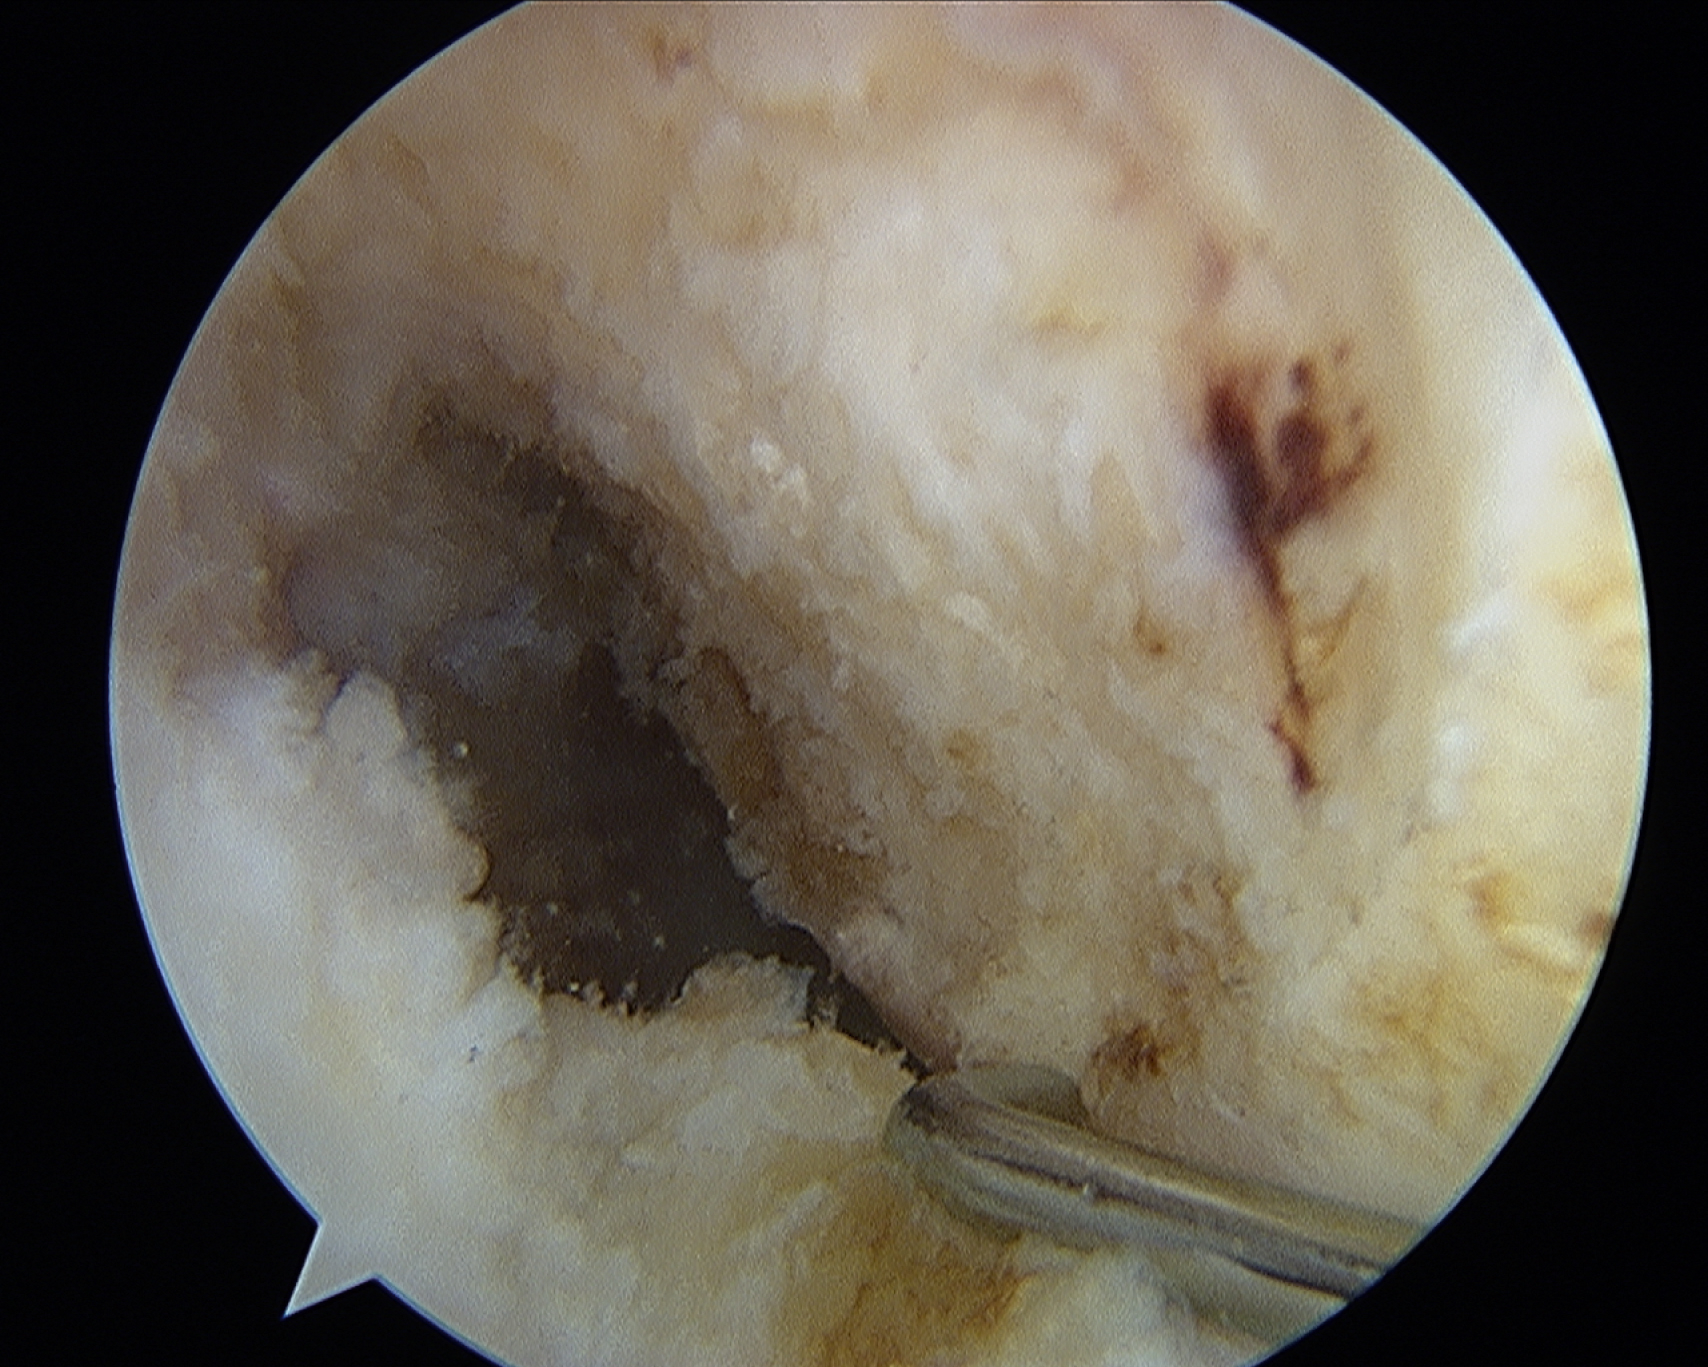

Viewing the notch from the lateral portal to assess the ACL insertional anatomy is a challenge. The lateral portal view allows a good evaluation of height within the notch but little perspective on depth within the notch. The medial portal provides an excellent view of the anatomy ( Fig. 49.2 ), but the medial portal is a working portal and generally only used for viewing when verifying an anatomic location. Thus the site for a femoral tunnel placement is identified when viewing from a lateral portal, which has limited perspective. Multiple strategies have evolved to address this challenge. Generally these have relied upon either identifying the ACL remnants, identifying the intercondylar ridge, or using a clockface analogy. The author has found identification of ACL remnants and the intercondylar ridge to be inconsistent, and the use of a clockface analogy has been inexact.

This view from the medial portal demonstrates perspective on height and depth within the notch. The lateral intercondylar ridge and remnants of the anterior cruciate ligament are often hard to identify as landmarks for femoral tunnel placement.